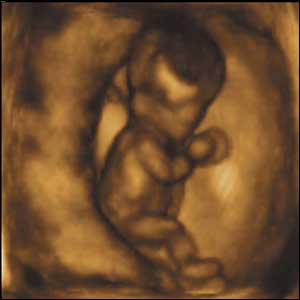

10 weeks gestation, 60mm from crown to rump.

2 of 10

At ten weeks gestation, this foetus can move her arms and legs with a range of movements that are fluid and supple.